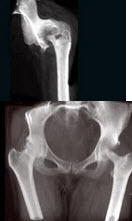

7、单项选择题

女,10岁,左大腿疼痛,夜间加重,肿胀明显,结合图像,最可能的诊断是()

A.成骨性骨转移

B.化脓性骨髓炎

C.骨肉瘤

D.骨化性肌炎

E.以上都不正确

A.上颌骨

102、单项选择题

女,27岁,双侧髋部疼痛,肿胀2月余,有髋部外伤史,结合图像,最可能的诊断是()

A.股骨颈骨折

B.股骨头骨折

C.慢性骨髓炎

D.慢性骨脓肿

E.骨结核